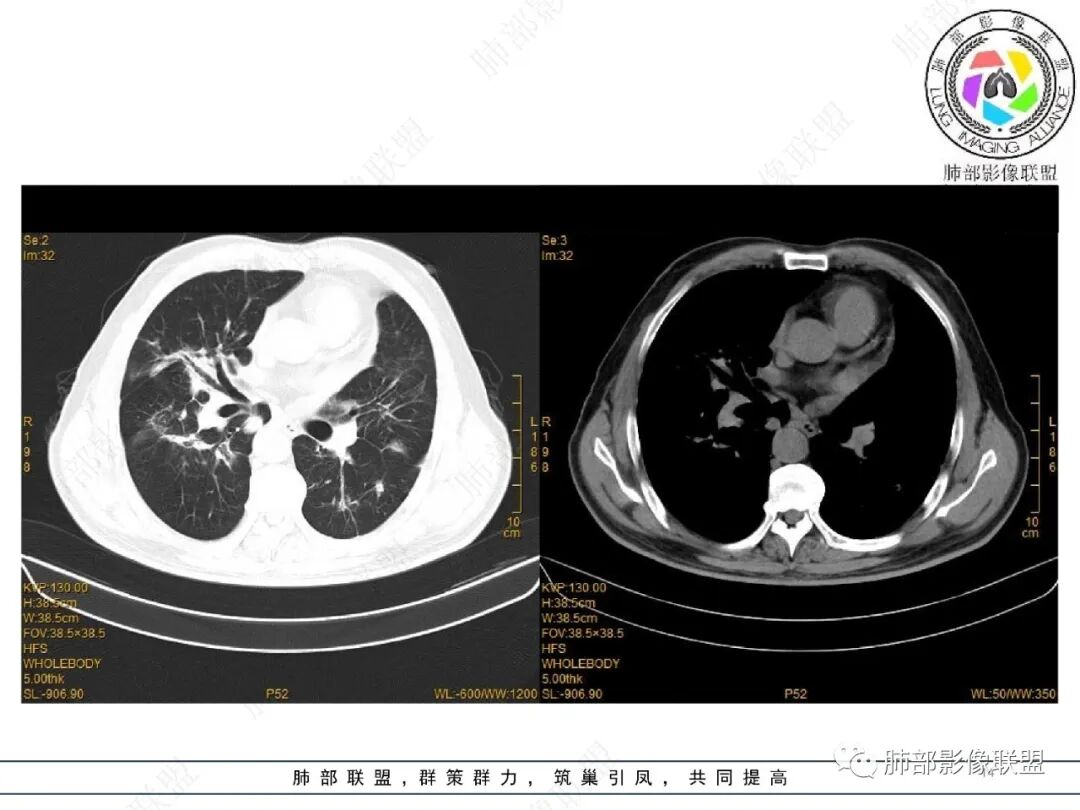

2022.2.17CT显示两肺中内带多发结节影、斑片影、条索影,部分病灶侧向融合与胸膜平行。部分病灶沿着支气管血管束分布、其内支气管稍扩张。部分病灶呈反晕征。大部分病灶边界显示清晰,部分病灶周围可见边界不清的GGO。2022.4.12CT显示两肺中内带多发结节影、条索状、条带状高密度影,边界收缩平直凹陷,大部分病灶沿着支气管血管束分布,亦有位于胸膜下侧向融合与胸膜平行的病灶。总体与第一次CT对比两肺病灶明显吸收。